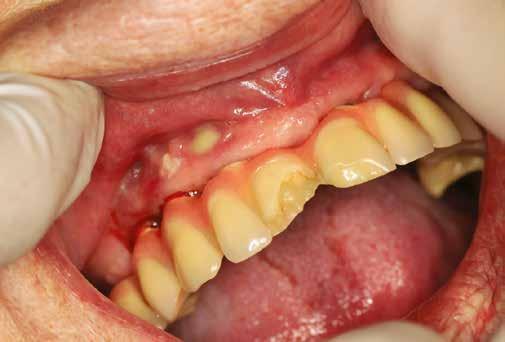

Mind a hat implantátum esetén kétlépcsős műtétet végeztünk. Minden sebészeti eljárást bódítás, illetve preoperatív szisztémás antibiotikus terápia nélkül végeztünk. A négy eset közül kettőnél leukocitában és vérlemezkében gazdag fibrint (L-PRF) alkalmaztunk a beavatkozás során (IntraSpin, BioHorizons; 2. táblázat). Minden esetben a pontos CERALOG menetvágási (maximum 15 ford./perc) és fúrási (maximális fúrási fordulatszám: 550–800 ford./perc) protokollt követtük. Az összes implantátumot manuálisan helyeztük be 35 Ncm maximális nyomatékkal. Az implantátumokba PEEK zárócsavar került (2. ábra). A lágyszövetet atraumatikus, felszívódó varrattal, szorosan zártuk/összevarrtuk. A műtétek után szövődmények nem jelentkeztek. A pácienseket arra kértük, hogy a műtét utáni héten naponta kétszer öblögessenek klórhexidinnel (PERIO-AID, 0,05%, DENTAID). Az alsó állcsontnál három hónapos, a felső állcsontnál öt hónapos gyógyulási időt vettünk figyelembe. Három hónap (1. eset) és öt hónap (2., 3. és 4. eset) elteltével a műtétek második stádiumát helyi érzéstelenítés mellett végeztük. A gyógyu-

lási csavarokat (PEEK titáncsavarral) maximum 15 Ncm-rel húztuk meg (3–6. ábra). Az összes implantátum kiváló stabilitást mutatott (a mérésekhez Periotestet használtunk, a Medizintechnik Gulden jóvoltából), és teljesen osszeointegrálódott. Ezt a radiológiai vizsgálatok is megerősítették.

3. a–b ábra: Röntgenfelvételek három hónap után (a) és a gyógyulási csavarok behelyezve (b, 1. eset).

4. a–b ábra: Röntgenfelvételek öt hónappal később (a) és a gyógyulási csavarok behelyezve (b, 2. eset).

5. a–c ábra: Röntgenfelvételek öt hónappal később (a) és a gyógyulási csavarok behelyezve (b és c, 3. eset).

6. a–b ábra: Röntgenfelvételek öt hónappal később (a) és a gyógyulási csavarok behelyezve (b, 4. eset).